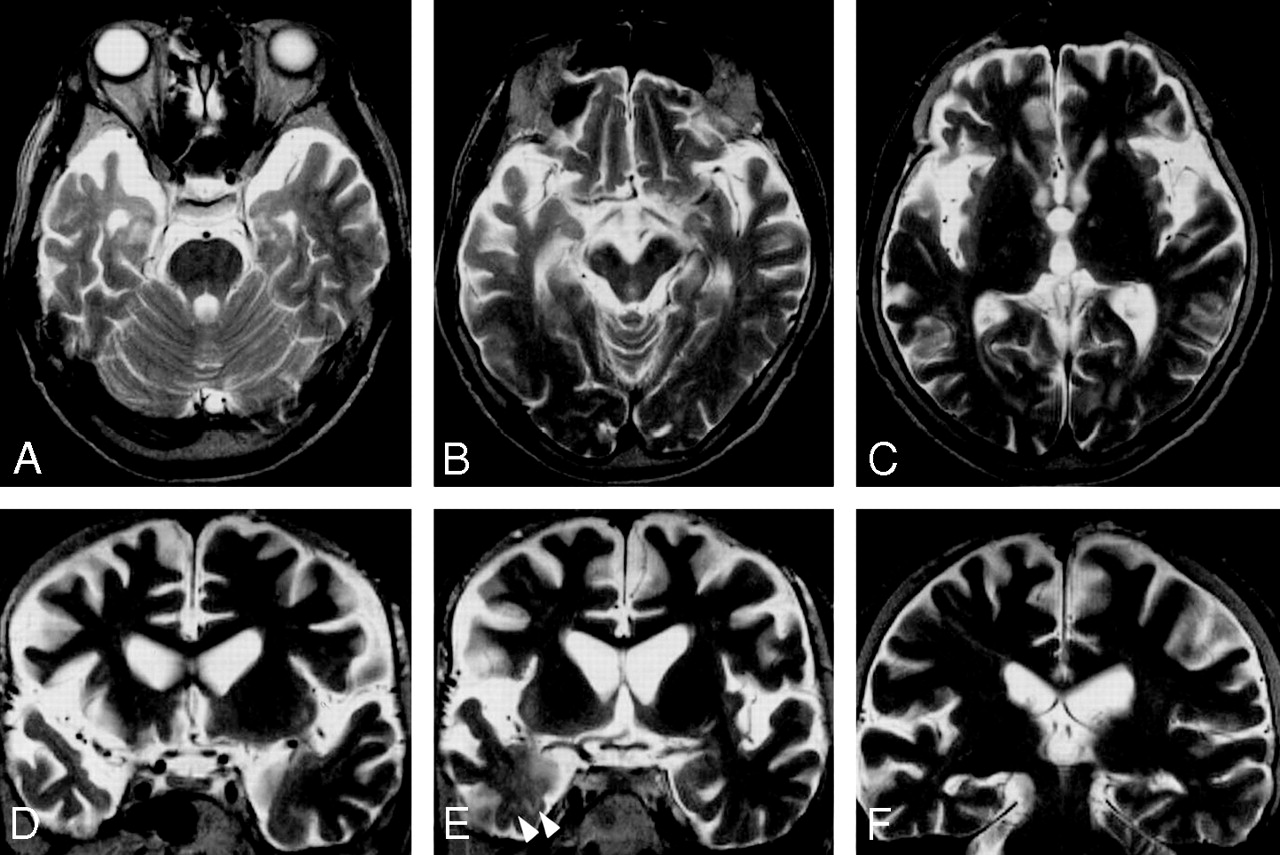

The findings on antemortem and postmortem T2-weighted MR imaging in 3 cases are summarized in Table 2. These images showed atrophy in the anteromedial part of the bilateral temporal lobes, more marked on the right side, but atrophy of the frontal lobes was not apparent in cases 1 (Figs 1A–F) and 2 (Fig 2). In case 3, postmortem T2-weighted MR images showed symmetric atrophy of the frontal and temporal lobes, more markedly in the anteromedial part of the temporal lobes (Figs 3A–F). Atrophy was seen mainly in the cerebral cortices, and changes in signal intensity were not detected in the cerebral cortices on both antemortem and postmortem T2-weighted images in each case (Figs 1A–F, Fig 2, and Figs 3A–F). Changes in signal intensity were seen in the cerebral white matter in case 2 on antemortem T2-weighted images but were seen in each case on postmortem T2-weighted images. In case 1, postmortem T2 hyperintensities were seen in the anteromedial white matter of the temporal lobes, where linear subcortical hyperintensities were also seen, more markedly on the right side (Figs 1D–F). In case 2, antemortem T2-weighted images showed focal and faint hyperintensities in the subcortical white matter in the anteromedial part of the right temporal lobe (Fig 2E, arrowheads), but postmortem T2-weighted images showed hyperintensities in the subcortical white matter of both the frontal and temporal lobes. Postmortem T2-weighted images in case 3 showed T2-hyperintensities in the subcortical and deep white matter of the frontal and temporal lobes (Figs 3A–F). In each case, atrophy and changes in signal intensity were not found in the corticospinal tracts in the cerebrum and brain stem and in the substantia nigra on both antemortem and postmortem T2-weighted images (Fig 3).

Case 1: Coronal T2-weighted MR images obtained 1 year after the onset of ALSD (A–C). AtNOphy is seen in the anteromedial part of the bilateral temporal lobes, especially on the right side, but not apparent in the frontal lobes. Postmortem coronal T2-weighted MR images (D–F) show asymmetric atrophy of the temporal lobes, more severe on the right side. T2 hyperintensities are also seen in the anteromedial part of the right temporal white matter. G, The right temporal lobe in (D) shows linear hyperintensity in the subcortical white matter (arrowheads). H, A Klüver-Barrera-stained section corresponding to boxed area in (G) shows laminar pallor of the subcortical white matter (arrowheads). I, Boxed area in (H) shows spongiform changes in the cortex (arrows). J, Histologic examination of the area in (I) shows spongiform changes with neuronal loss and gliosis. H, Klüver-Barrera stain x 20. I, hematoxylin-eosin, x 100. J, GFAP, x 200. K, Right temporal lobe in (E) shows hyperintensities in the medial part of the temporal white matter, especially in the underlying U-fibers (arrowheads). L, A Klüver-Barrera-stained section corresponding to (K) reveals pallor in the medial part of the temporal white matter, especially in the underlying U-fibers (arrowheads). M, A Holzer-stained section corresponding to (K) reveals gliosis in the medial part of the temporal white matter, especially in the underlying U-fibers (arrowheads). N, O, Histologic examination of normal signal intensities on MR image (K–M, circles) shows no apparent degenerative changes. P–R, Histologic examination of the U-fibers (arrows) in (K–M) shows loss of myelin (P) and axons (Q) with moderate gliosis (R). N, P, Klüver-Barrera stain. O, Q, Bielschowsky stain. R, GFAP stain. N, O, P, Q, R, x 200.

Case 2: Axial (A–C) and coronal (D–F) T2-weighted MR images obtained 4 months before death. Asymmetric cerebral atrophy is seen in the frontal and temporal lobes, more marked on the right side. Atrophy is more prominent in the anteromedial part of the temporal lobes. Focal and faint hyperintensities are seen in the subcortical white matter in the anteromedial part of the right temporal lobe (arrowheads in E). No definite T2-hyperintensities are seen in the corticospinal tracts in the internal capsules, cerebral peduncles, and pontine base. Change in signal intensity of the substantia nigra is also not seen.